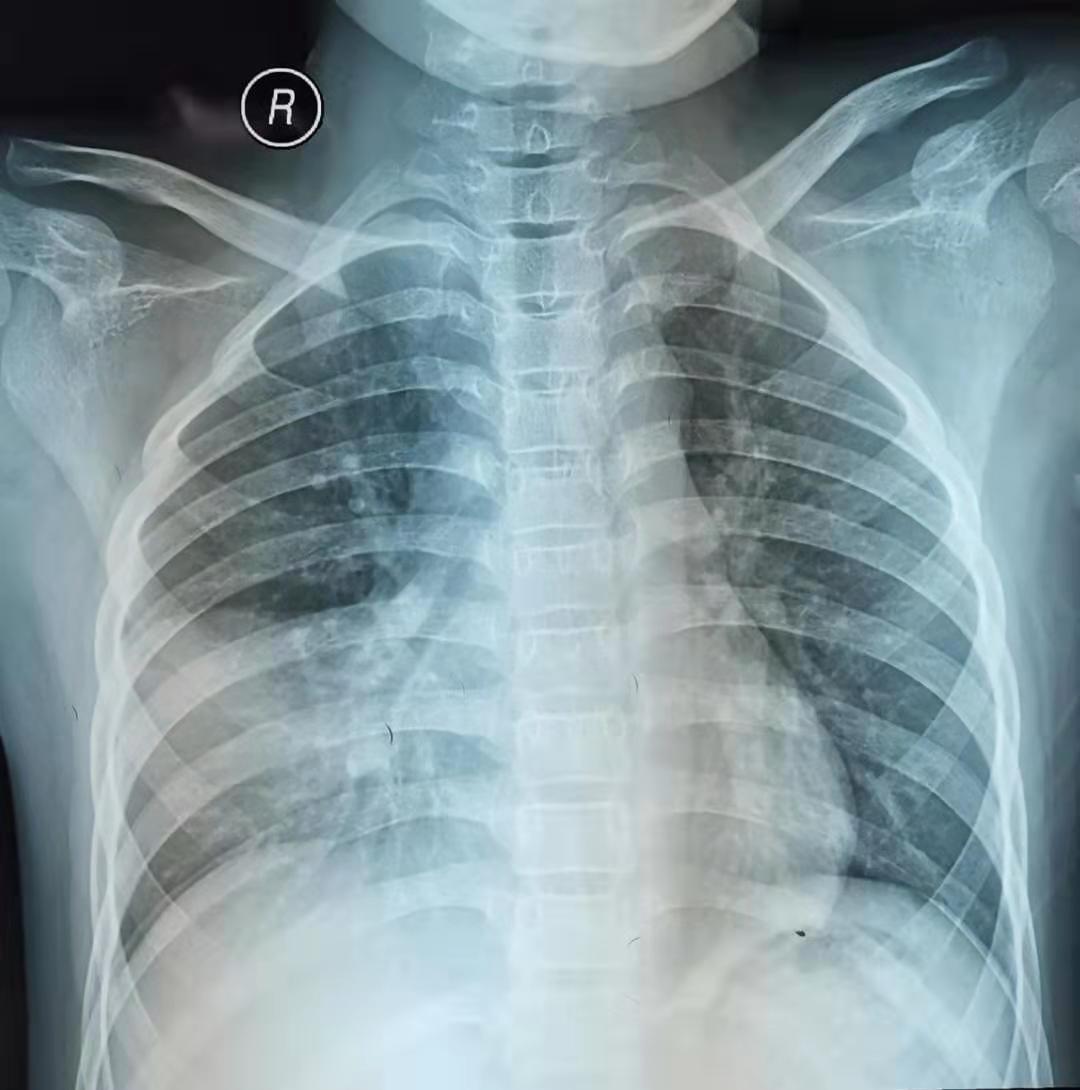

我一看检查结果,血象不高,中性粒细胞为主,C反应蛋白稍高,胸片右下肺一大片实变影,再一查体,右下肺呼吸音低,典型的支原体肺炎。我耐心的安慰家长。孩子的诊断没错,就是支原体肺炎,同时家长说明了为什么短期用药不见效的原因。

学龄期或学龄前期儿童有发热、咳嗽,肺部听诊无湿罗音,血常规白细胞不高或轻度升高或降低,中性粒细胞为主,CRP正常或增高,胸片可见大片实变影,临床需高度怀疑支原体肺炎。血清支原体抗体IgM滴度持续≥1:160或双份血清(间隔两周)抗体滴度上升4倍或下降为原来的1/4,一般认为是支原体感染。分子生物学检测支原体RNA阳性可诊断支原体感染。确诊的金标准是支原体培养阳性,但其培养时间长,故临床意义不大。